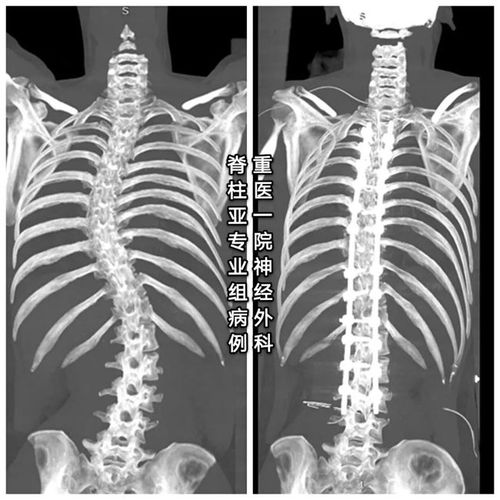

病例分享|成人脊柱侧弯畸形一例|腰椎|侧凸|矫形术